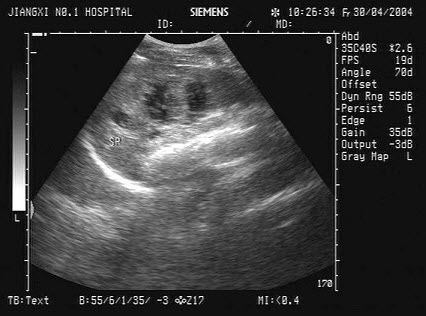

10、单项选择题

男、30岁,体检时发现脾门处光团,根据超声声像图诊断为()

A.副脾

B.淋巴结

C.转移癌

D.脾脓肿

E.左肾上腺肿瘤